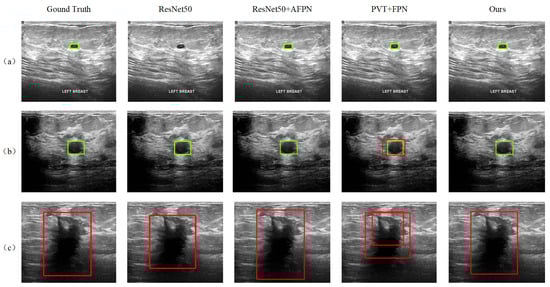

3.2.3. Visualization of Detection Results

In addition to the quantitative AP-based evaluation, the detection results of the proposed method are also visualized and qualitatively analyzed. It is shown that our model is better at detecting tumors of different scales and properties. Figure 8 shows the results of some sample images, where samples (a) and (b) contain benign tumors with large-scale differences, marked by the green boxes, while sample (c) contains a malignant tumor, marked by the red boxes. The detection results of the three reference models, ResNet50, ResNet50+AFPN, and PVT+FPN, that performed better in Table 1 are also given in the figure. The ResNet50 model fails to detect the small benign tumor in sample (a). In sample (b), although all models successfully detected the benign tumor, the PVT+FPN model additionally detected a malignant tumor in almost the same (slightly larger) location, resulting in a contradictory result. The introduction of AFPN into ResNet50 effectively improves the detection performance, and the ResNet50+AFPN model achieves correct results in all three samples (see the third column). In contrast, the DETR model performs less effectively in detecting large malignant tumors, often producing overly broad bounding regions that reduce localization precision when compared with our method. Compared to ResNet50+AFPN, our model demonstrates more accurate tumor localization.

Figure 8.

Tumor detection results for three samples in the test set: Sample (a) contains a small benign tumor, Sample (b) contains a medium-sized benign, Sample (c) contains a malignant tumor.